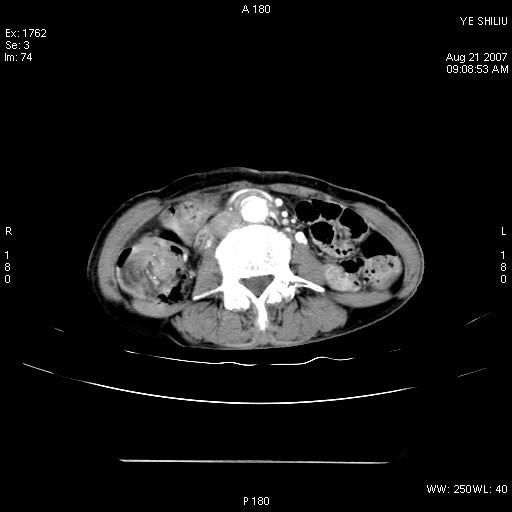

回盲部腺癌

患者,女,74岁,腹痛一周。开始为脐周疼痛,后转移至右下腹。治疗经过:门诊拟急性阑尾炎收内科治疗,b超示胆囊结石、胆囊炎转外科。拟行胆囊切除术前检查ct。